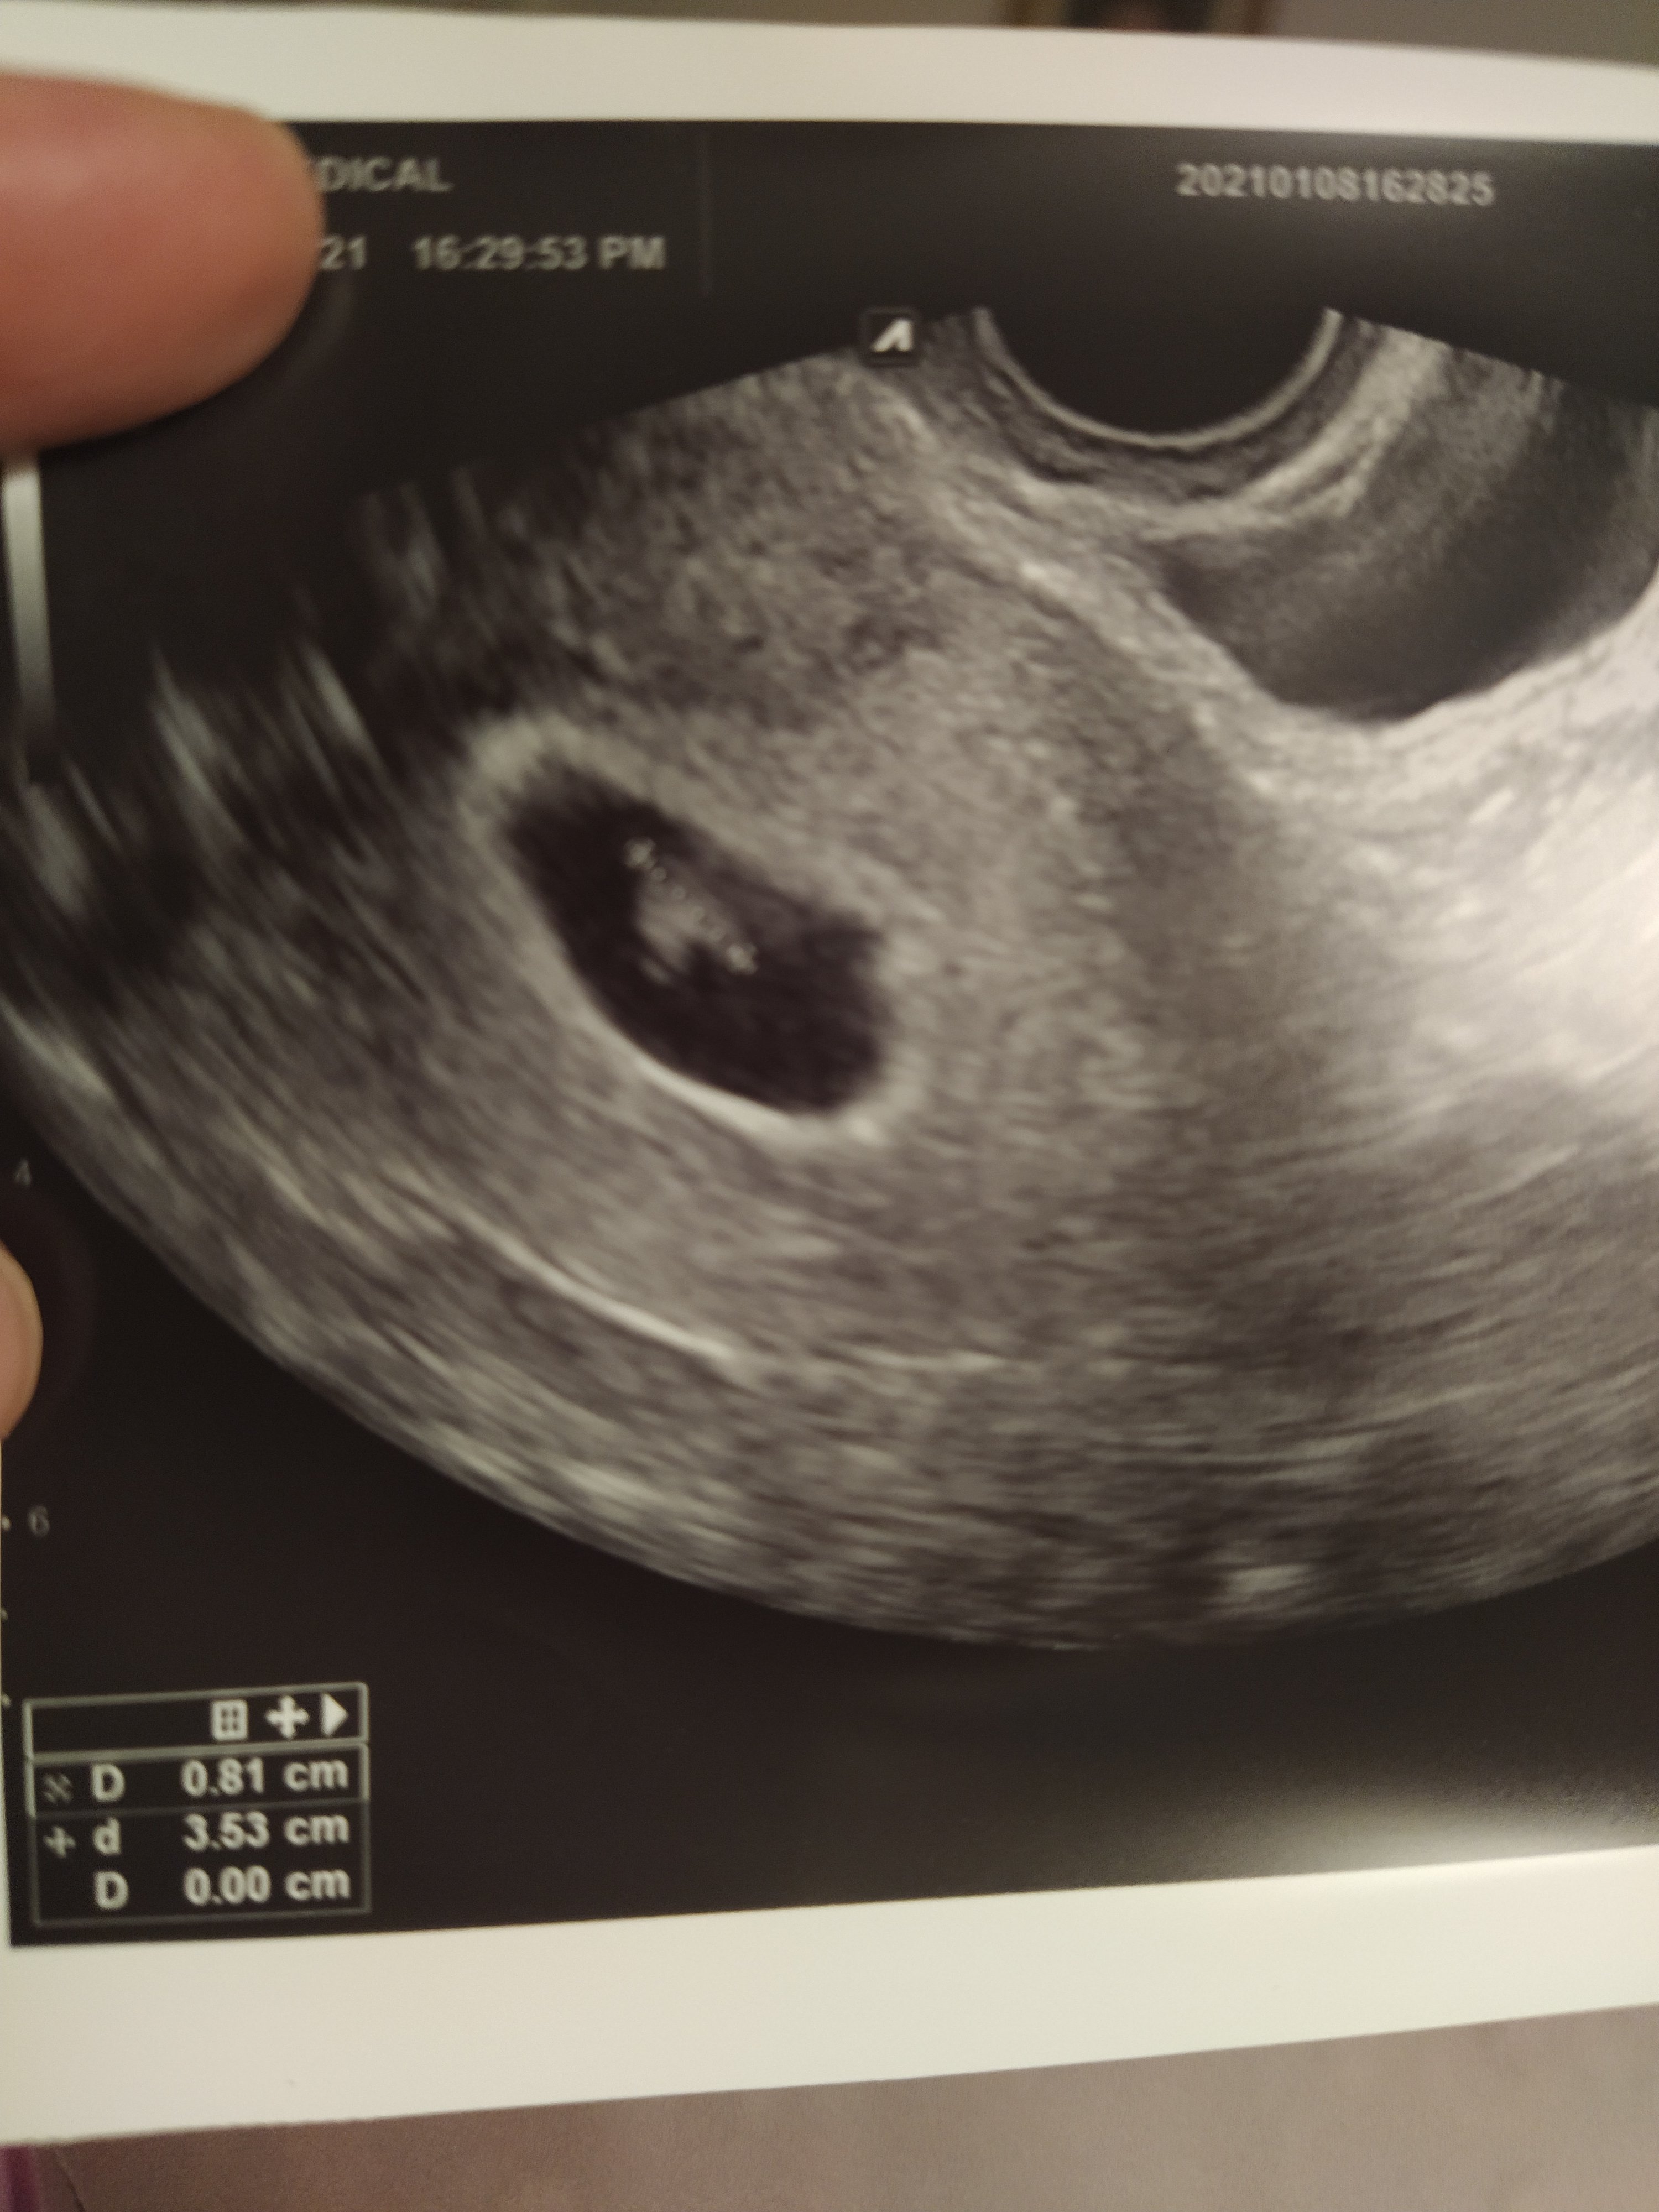

Ja biorę, nie mam bólu głowy, generalnie nie odczuwam żadnych dolegliwości po nim.Czesc! Przebrnęłam przez cały wątek i postanowiłam się ujawnićtermin z aplikacji mam na 18 sierpnia. W poniedziałek byłam na pierwszej wizycie i był zarodek z serduszkiem

bardzo się ucieszyłam bo we wrześniu stwierdzono u mnie poronienie zatrzymane niestety, serduszko w ogóle nie zaczęło bić. Niestety doktor znalazła też krwiaka :/ co prawda oddalony od pęcherzyka ale i tak się zaniepokoilam

Ja cały czas mam jakieś plamienia, a na USG wszystko okJa już po wizycie, wszystko ok, zarodek widać,już też biło

Zobacz załącznik 1223796